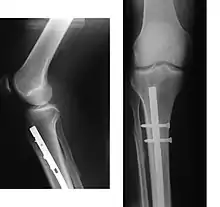

Since bone healing is a natural process that will occur most often, fracture treatment aims to ensure the best possible function of the injured part after healing. Bone fractures typically are treated by restoring the fractured pieces of bone to their natural positions (if necessary), and maintaining those positions while the bone heals. Often, aligning the bone, called reduction, in a good position and verifying the improved alignment with an X-ray is all that is needed. This process is extremely painful without anaesthesia, about as painful as breaking the bone itself. To this end, a fractured limb usually is immobilized with a plaster or fibreglass cast or splint that holds the bones in position and immobilizes the joints above and below the fracture. When the initial post-fracture oedema or swelling goes down, the fracture may be placed in a removable brace or orthosis. If being treated with surgery, surgical nails, screws, plates, and wires are used to hold the fractured bone together more directly. Alternatively, fractured bones may be treated by the Ilizarov method which is a form of an external fixator.

Surgical methods of treating fractures have their own risks and benefits, but usually, surgery is performed only if conservative treatment has failed, is very likely to fail, or is likely to result in a poor functional outcome.[39] With some fractures such as hip fractures (usually caused by osteoporosis), surgery is offered routinely because non-operative treatment results in prolonged immobilisation, which commonly results in complications including chest infections, pressure sores, deconditioning, deep vein thrombosis (DVT), and pulmonary embolism, which are more dangerous than surgery.[40] When a joint surface is damaged by a fracture, surgery is also commonly recommended to make an accurate anatomical reduction and restore the smoothness of the joint.